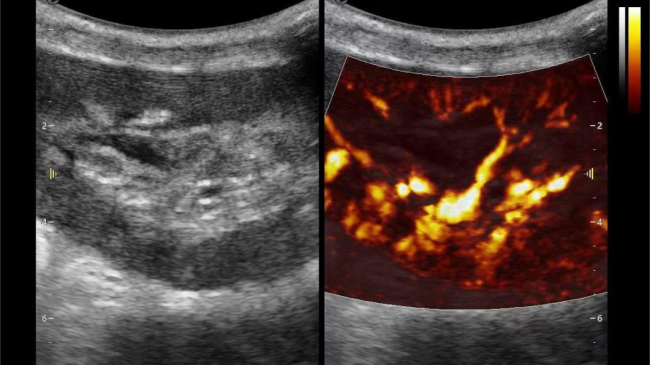

2) 可检测20-50μm级细小血管低速血流信号,能看清头发丝1/2粗细的微血管;

超微视血流显像显示肾脏五级血管

肾脏的灌注评估,RI/VI量化数据

超微视血流显像评估肾移植术后灌注情况

这一项无创、无辐射操作简便且无需造影剂的黑科技,相当于用"高速摄像机"记录血液细胞的运动轨迹,让血管并发症"无处遁形。

从术前评估到术中到术后,再到终身监护,当20-50μm级的超微血流信号在屏幕上跳动,我们看到的不仅是技术的精进,更是生命的律动。iPlane Vascular正在重新定义肾移植监护的标准——让医生拥有了"显微视力",让每一个微小血管的异常都无所遁形,让每一次免疫排斥的萌芽都被及时扼制。